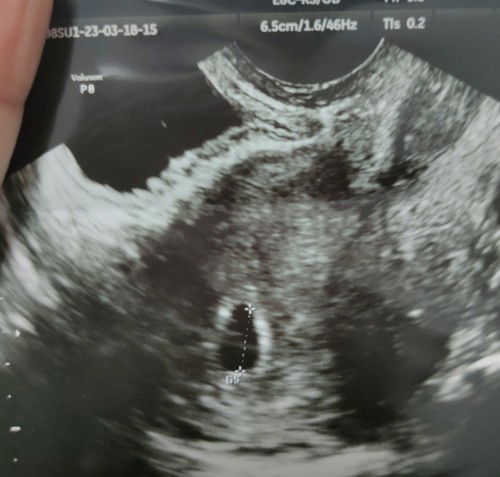

6 week 4วัน ไปฝากที่รพ. ซาวด์หน้าท้อง ยังไม่เจอตัวอ่อน หมอสันนิษฐาน2 อย่างคืออายุครรภ์น้อยกับอาจจะท้องลม🥹 อยากถามแม่ๆว่า ตอน6วีคบ้านไหนยังไม่เจอน้องบ้างคะ **ของเราตอน5วีคไปซาวด์ที่คลินิค เจอถุงตั้งครรภ์กับถุงไข่แดง ซาวด์ผ่านช่องคลอดค่ะ**#ท้องแรกคะ #ขอคำแนะนำหน่อยค่ะ #ขอบคุณสำหรับคำตอบค่ะ #คุณแม่ๆช่วยแนะนำหน่อยค่ะ